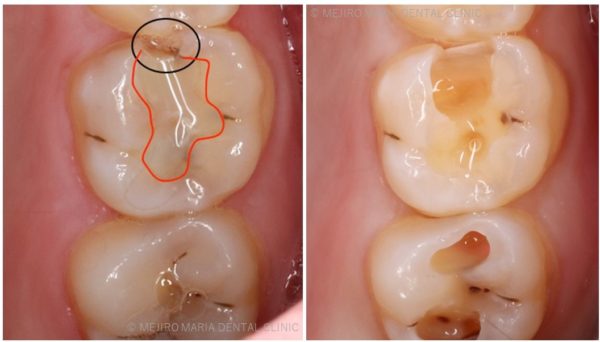

赤枠で囲んだ箇所はレジン充填されているところ

※右写真:虫歯を除去したところ

辺縁隆線(黒丸の部分)の歯質が薄くなっていると歯質が欠けたり、劣化により2次カリエス(治療後再度虫歯になる)の原因となります。また、歯と歯の間の形が不適切だと食べ物が詰まりやすくなり、歯周病や虫歯の原因になります。その為、歯冠形態が適切に再現されない場合は型取りを行い、しっかりとしたインレー(詰め物)などで修復する必要があります。